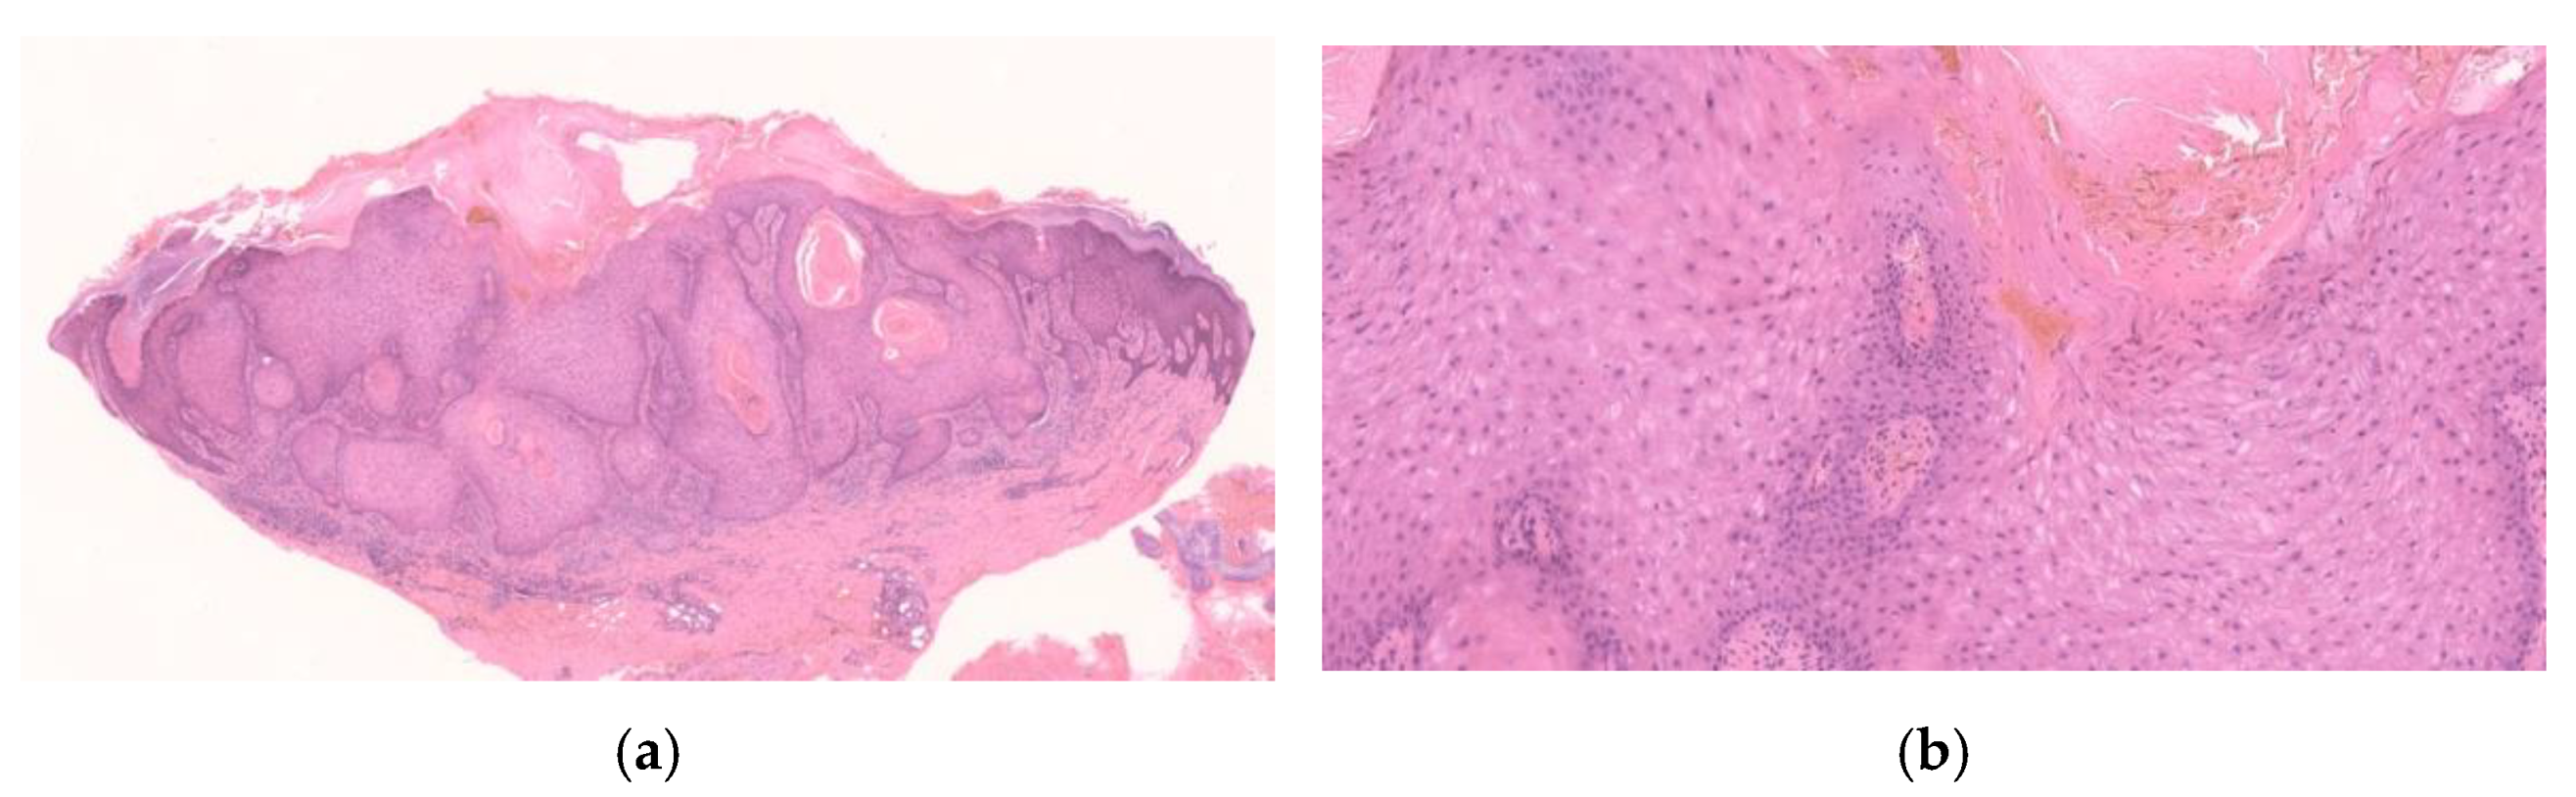

2.2.3. Early/Proliferative Stage